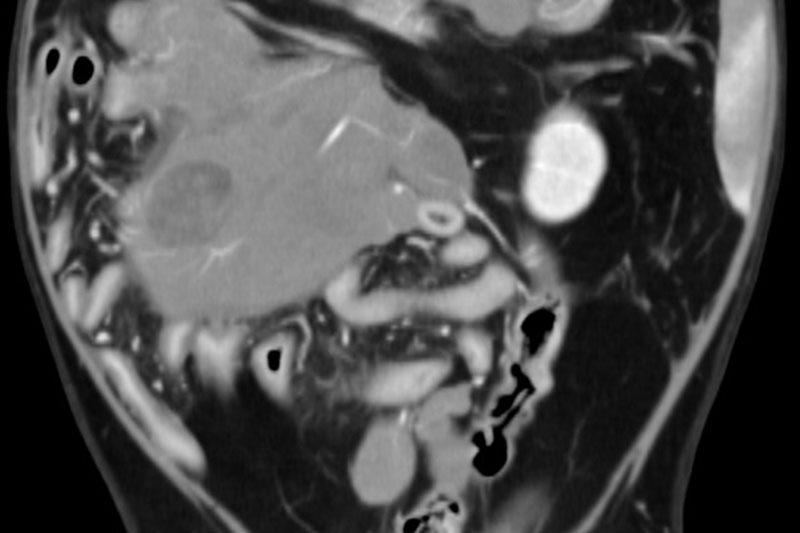

| 복부 | 간, 비장, 신장, 위장관 종양 및 결석, 부신, 림프절 등 |

복부 장기의 종양, 염증, 결석, 기형 등 고해상도 분석